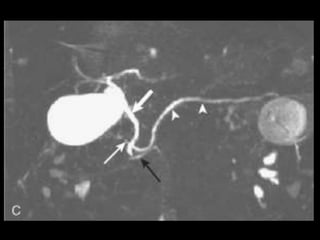

Pâncreas bífido

Mais comum variante congênita do pâncreas,

encontrada em 5% a 14% da população;

Caracteriza-se pela não fusão dos ductos dorsal e

ventral, que drenam separadamente;

Drenagem predominante pelos ductos

dorsais(Santorini) para a papila menor.

O espectro de sintomas clínicos é amplo, variando

de assintomático a dores abdominais leves e a uma

pancreatite aguda, aguda recorrente ou crônica.

A CPER tem sido tradicionalmente considerada o

padrão ouro para o diagnóstico dessa condição;

Canulação da papila maior: ducto ventral mais

curto que o normal(1 a 4 cm), não cruza a linha

média e conserva a sua ramificação normal;

Canulação da papila menor: sistema dorsal

permeável drenando o colo, o corpo e a cauda do

pâncreas;

CPRM: 73% de acurácia;

TCMD: pode ser diagnóstica com o uso de

reconstruções multiplanares.